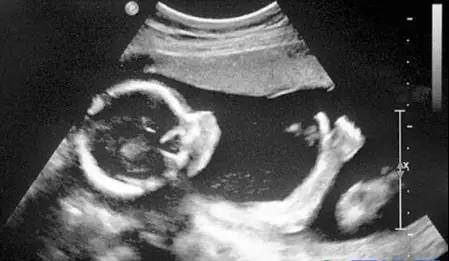

B超:像挑西瓜前敲一敲

B超的原理是用超聲波穿透人體,當(dāng)聲波遇到人體組織時會產(chǎn)生反射波,通過計算反射波成像。就像挑西瓜一樣,邊敲邊看顯示病灶情況。